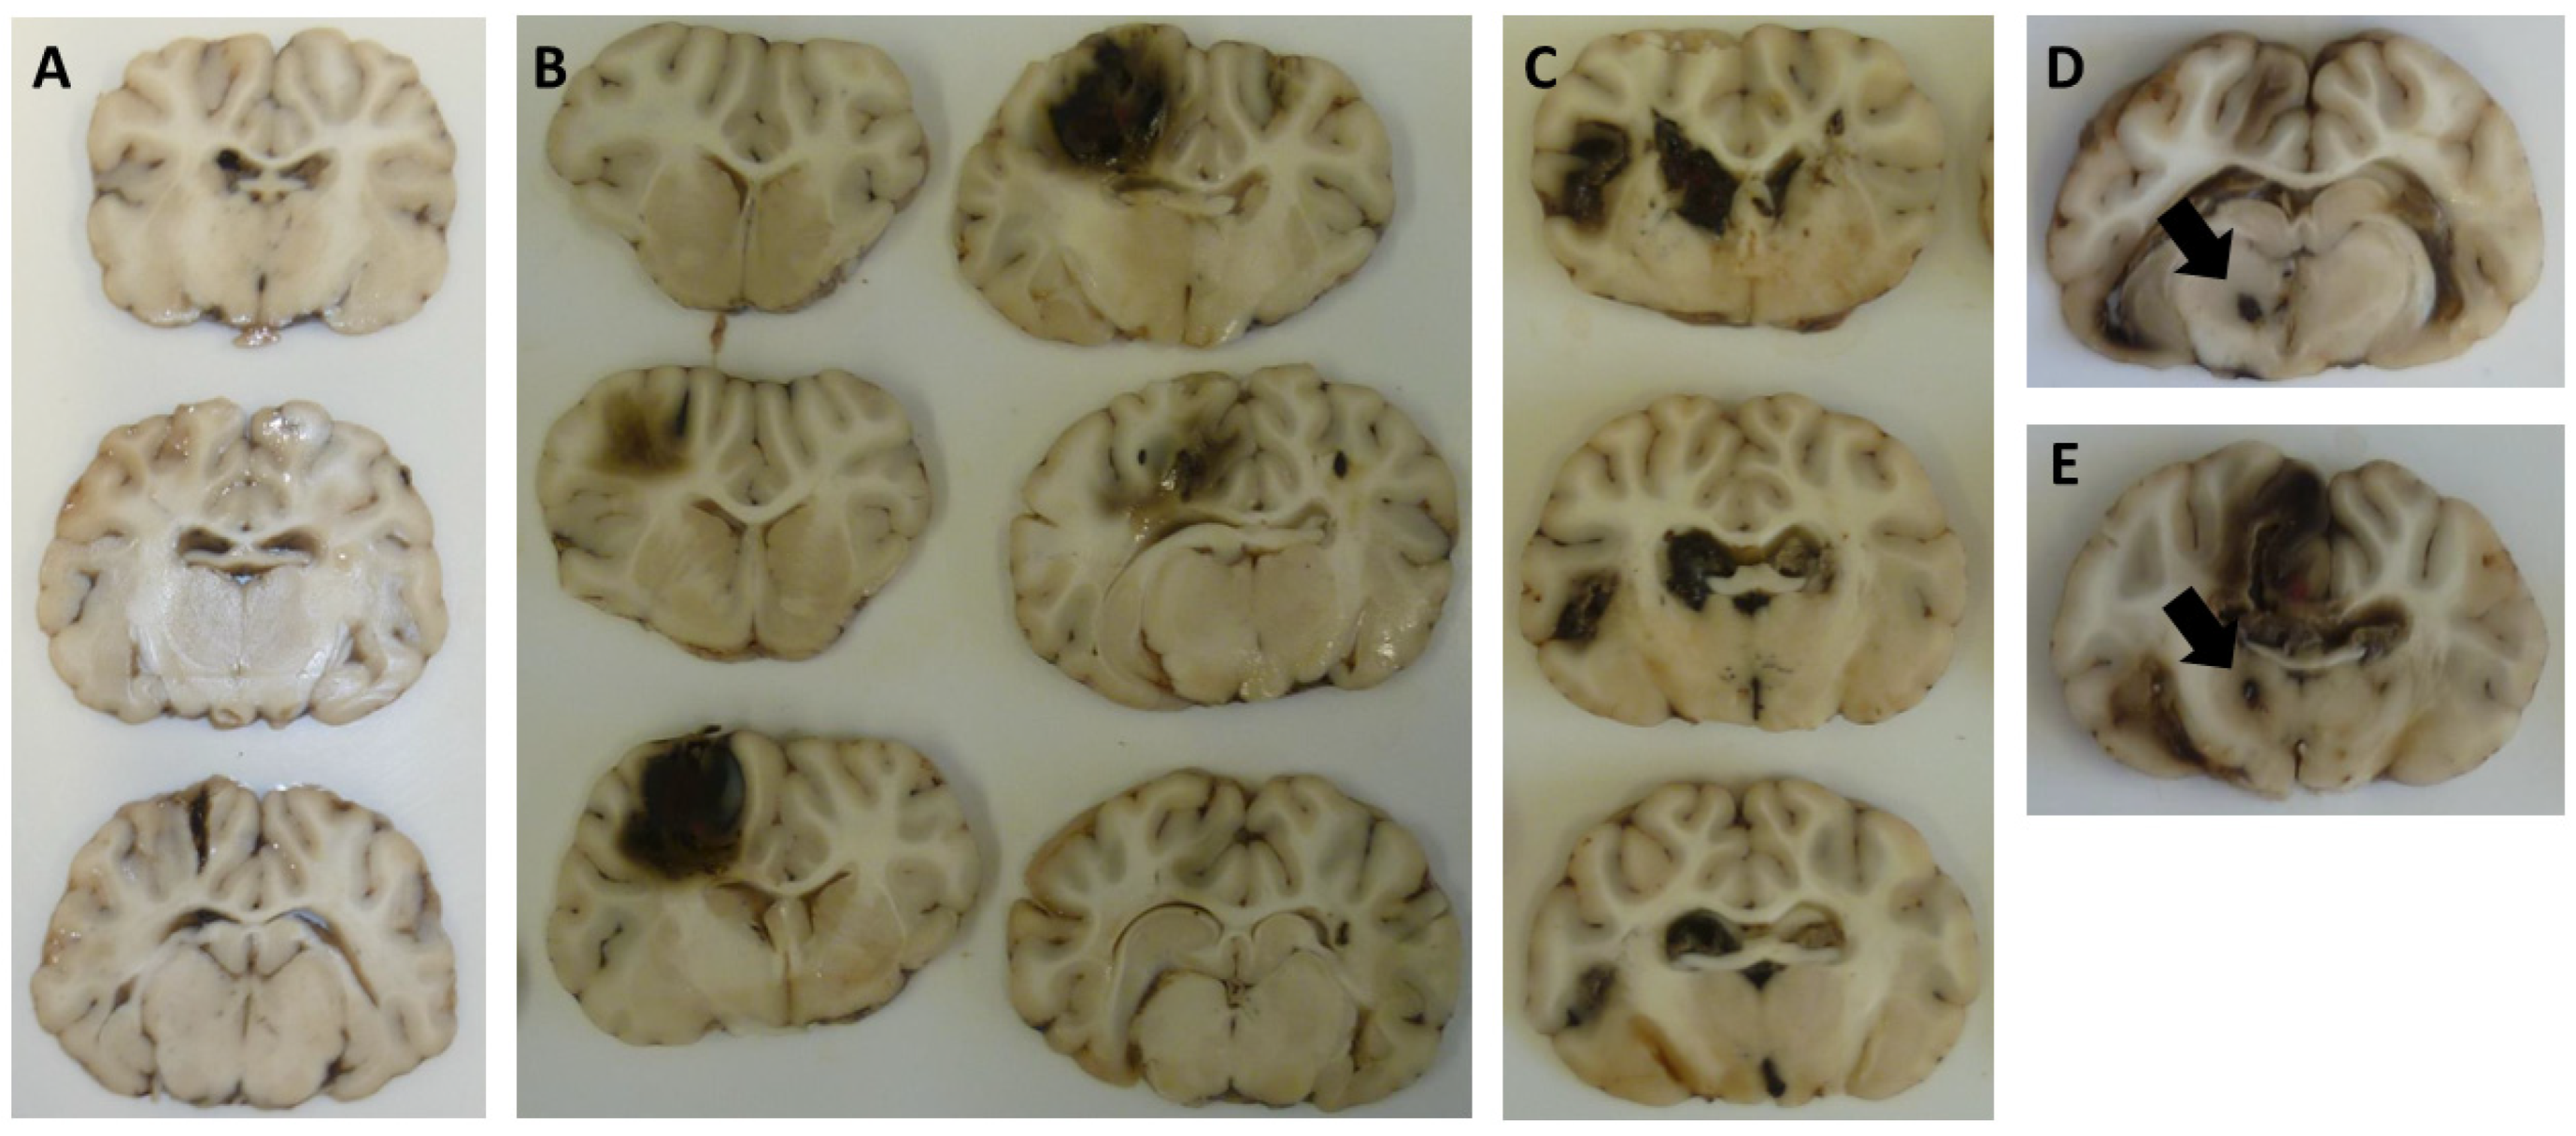

| Brainstem injury, N (%) | 0 (0) | 4 (9.1) | 16 (36.4) | 20 (45.5) | <0.001 1 | |

| Basalganglia injury, N (%) | 0 (0) | 8 (18.2) | 16 (36.4) | 24 (54.5) | 0.011 1 | |

- Colquhoun, I.R.; Rawlinson, J. The significance of haematomas of the basal ganglia in closed head injury. Clin. Radiol. 1989, 40, 619–621. [Google Scholar] [CrossRef]

- Adams, J.H.; Doyle, D.; Graham, D.I.; Lawrence, A.E.; McLellan, D.R. Deep intracerebral (basal ganglia) haematomas in fatal non-missile head injury in man. J. Neurol. Neurosurg. Psychiatry 1986, 49, 1039–1043. [Google Scholar] [CrossRef] [PubMed]